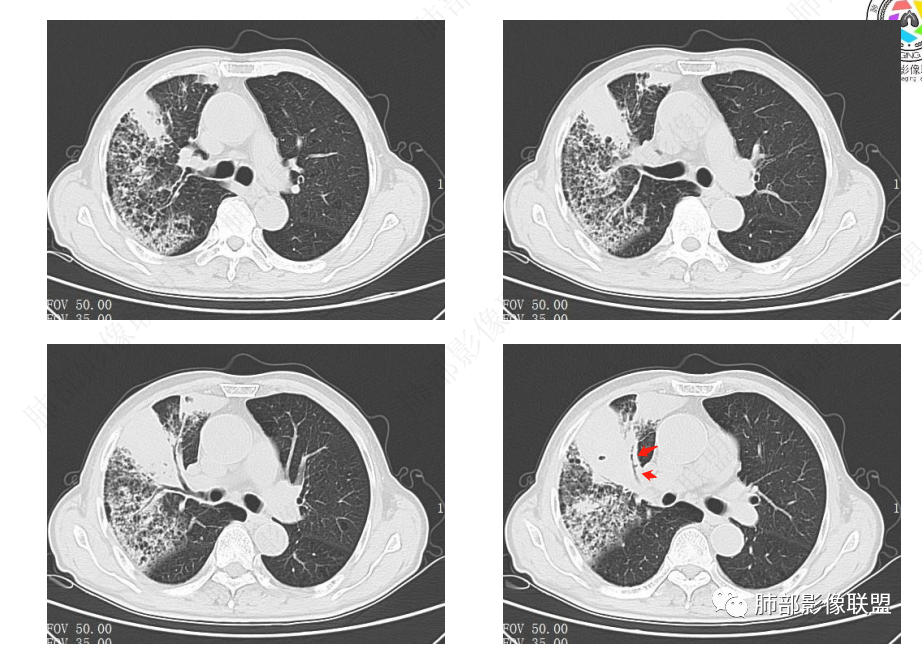

右肺上叶实变,宽基底与胸膜相连,邻近胸膜积液,上叶支气管阻塞,不均匀强化,血管显示可,局部坏死环形强化,可见气泡,考虑慢性炎症伴脓肿,放线菌?鉴别腺癌

晨读悬浮气泡,跨叶,病程长,放线菌?

右肺上叶尖段大片状实变,近肺门侧支气管闭塞,并可见病灶内部有片状液化坏死区,有空泡气体,病灶紧贴胸膜,胸膜反应性增厚,伴有少见积液,增强扫描内部不均匀强化,血管走形正常。影像符合慢性化脓性感染。

右肺上叶大片实变影,内密度不均匀,可见坏死环形强化,支气管被粘液栓阻塞,首先考虑感染性病变,奴卡?放线菌感染?

右肺上叶大片实变,密度不均,近端环形强化并见空泡,病灶与胸膜广基相连,之间并可见积液,考虑放线菌,鉴别腺癌

晨读:右肺上叶实变,密度欠均匀,不均匀强化,内血管走形可,近端环形强化并见空泡,考虑放线菌可能,鉴别腺癌

右肺上叶实变,宽基底与胸膜相连,不均匀强化,血管显示可,局部坏死环形强化,可见气泡,考虑慢性炎症伴脓肿,放线菌?鉴别腺癌

首先看肺实变不张的范围,病灶由外向内,病灶未见强化,内多发小气泡,边缘环形强化,考虑慢性感染性病变,放线菌?曲霉菌球?

右主支气管周围多发淋巴结肿大融合(提示右主支气管有外受压变窄),右肺上叶尖前不张,内见支气管粘液栓和坏死及环形强化特点,邻近胸膜增厚及右肺上叶后段支气管扭曲及狭窄后扩张,周边索条纤维化,综合TB表现,超声支气管镜检查。

凝固性坏死,肉芽肿性炎症,放线菌可能

老年女性患者胸痛咳嗽半年多时间。右肺上叶大片状实性病灶,近端支气管受压变窄。病灶内部密度不均,伴有不均匀强化,有局灶坏死,以及有支气管造影征,胸膜面显示不行,伴有少量的积液,病灶有局部的膨胀,纵隔淋巴结增大。

病灶的主要特点支气管变窄,病灶内及淋巴结有血管的漂浮。淋巴瘤及腺癌的可能性大。鉴别诊断:奴卡或TB?

老年女性患者胸痛咳嗽半年多时间。右肺上叶大片状实性病灶,近端支气管受压变窄。病灶内部密度不均,伴有不均匀强化,有局灶坏死,以及有支气管造影征,胸膜面显示不清,伴有少量的积液,病灶有局部的膨胀,纵隔淋巴结增大。

晨读,中年女性,咳嗽半年,右肺上叶斑片影,可见坏死及环形强化,血管影走形自然,胸膜增厚积液,纵隔淋巴结增大,右肺上叶支气管阻塞,考虑慢性炎症伴局部脓肿形成,鉴别腺癌?淋巴瘤?

中年女性,咳嗽,咳痰半年,CRP升高,右肺上叶大片实变,密度不均匀,边缘部见类圆形低密度影,内夹杂气体影,增强后呈环形强化,病变内血管走形征象,边缘略毛糙,考虑①炎性伴脓肿形成②上叶支气管截断,恶性不除外,鳞癌?

右肺门结节,显著强化,内可见坏死及悬浮气泡,远端阻塞性肺不张,心脏纵隔右移,结节及不张内血管影走行自然,并可见粘液拴,隆突下淋巴结肿大,慢性病程,病变跨叶,首选感染性病变放线菌感染,其次鉴别腺癌

晨读:右肺上叶大片状实变影,血管走形自然,可见类圆形低密度区,其内可见气泡影,纵膈内可见肿大淋巴结显示。考虑慢性炎症并脓肿形成,放线菌可能。鉴别淋巴瘤、腺癌。